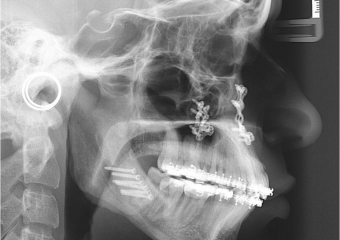

Telerradiografia inicial

Telerradiografia após a cirurgia